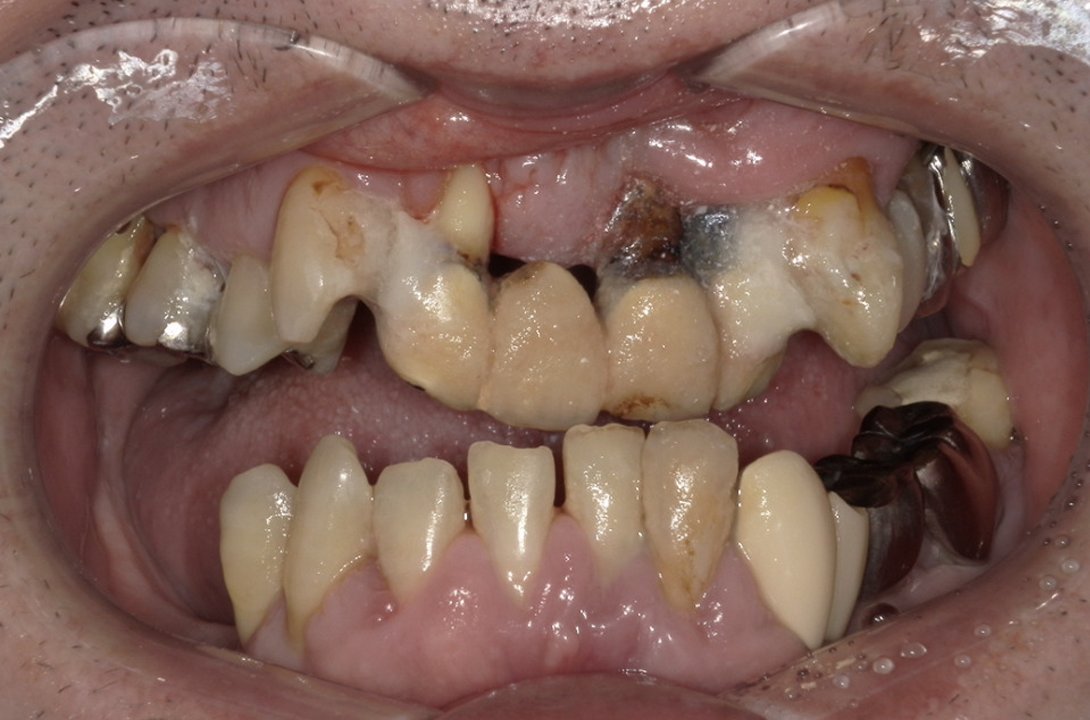

| 主訴 | 全体的にきれいにしたい |

|---|---|

| 治療内容 | 午前中に上下顎共に重度の歯周病、虫歯のため全ての歯を抜歯させていただき下顎はインプラントの土台を3本埋入し歯型を取り午後に上部構造(下顎全ての歯)を装着、上顎は一度総入れ歯を装着させていただきました。 治療が1日で完了しその日のうちに噛めるようになります。 |

| 治療期間 | 2回(1回目に資料取りをさせていただき2回目に下記の全ての治療をさせていただきました。) |

| 治療費 | 250万円 |

| 治療 リスク | 抜歯した部位などに関しては当日痛みが出ますので痛み止めなどを処方させていただきます |